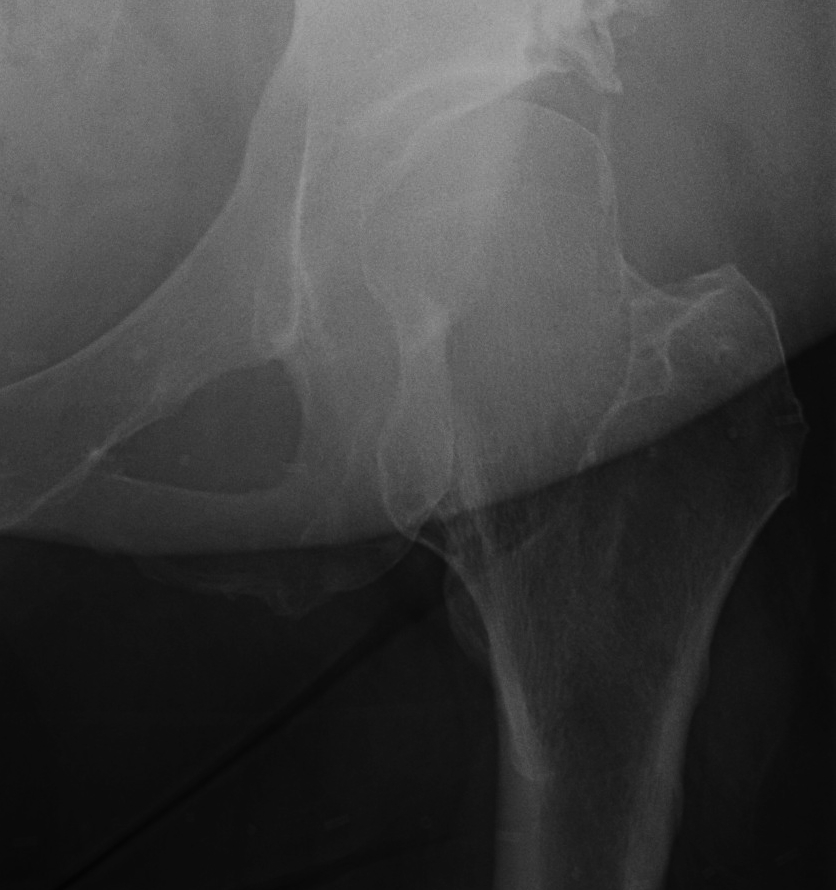

Hip

- coxa valga

- neck short & broad

Mult OC hipHip Osteochondroma

Hip HME

Issues

Coxa valga

Hip subluxation